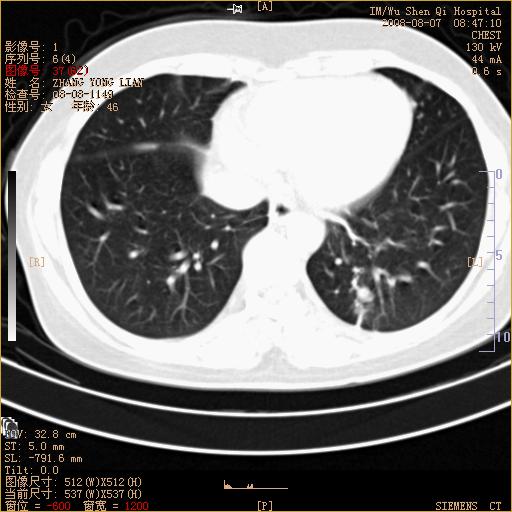

标题: CT15050:女,46岁,咳嗽胸痛一月余 [打印本页]

纵隔窗没发全,左下肺近胸膜处结节。有长毛刺,纵隔淋巴结增大,不排除恶性病变。

考虑左肺下叶后基底段周围型肺癌伴纵隔淋巴结转移可能性大。

左下肺ca并纵隔及左肺门区淋巴结转移。

脾脏低密度结节转移不排除。

1)考虑左肺下叶后基底段周围型肺癌伴纵隔淋巴结转移。2)脾内低密度灶,性质待定;不排除转移瘤可能。

考虑左肺下叶后基底段周围型肺癌伴纵隔及肺门淋巴转移。